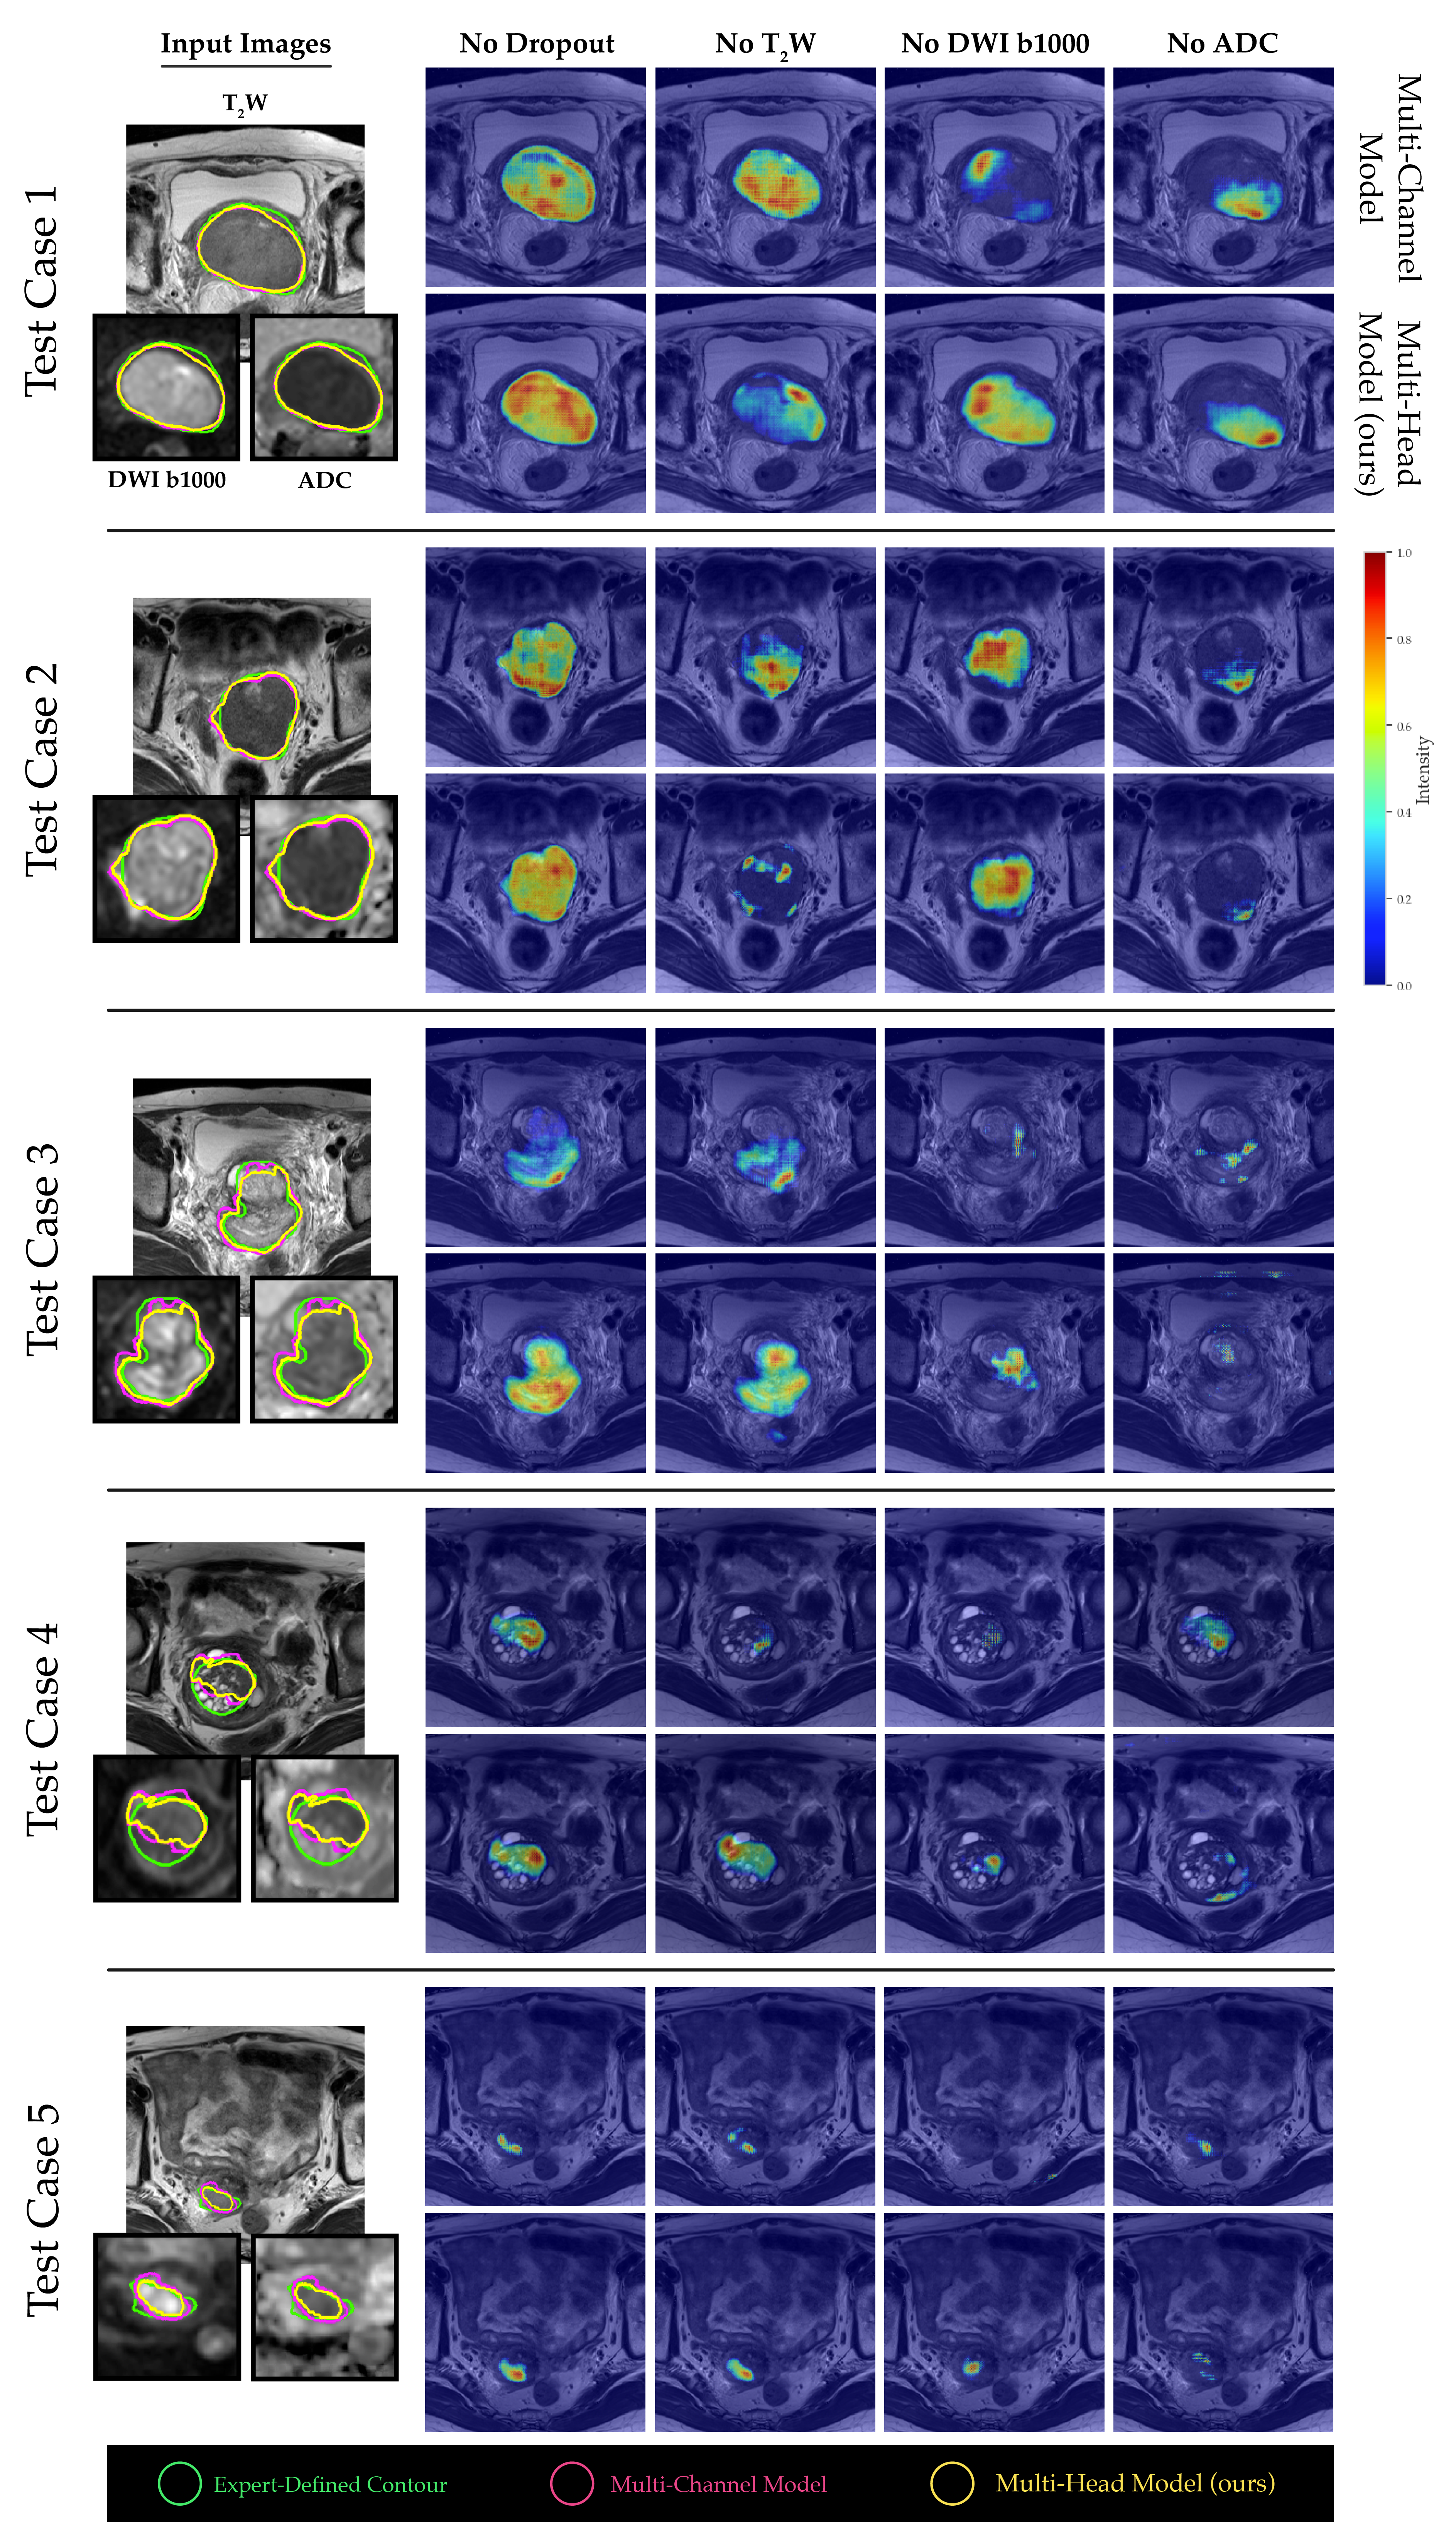

The channel sensitivity analysis conducted between the multi-channel and proposed multi-head model indicated that the multi-head model’s tumor segmentation performance significantly suffered when the ADC channel was removed (Figure 5). Moreover, the saliency maps generated from both models revealed that b1000 DWI images had a relatively minor impact on the overall tumor segmentation performance for larger tumor volumes, while T2W and ADC images were more crucial (see Figure 6, test cases 1 and 2). Conversely, for smaller and more challenging tumor masses, the absence of ADC values had a more pronounced adverse effect on the final outcome (see Figure 6, test cases 3-5).

Refer to caption

Figure 6: The normalized 3D GRAD-CAM saliency maps generated from the penultimate layer of models, highlighting the most relevant regions for segmentation under different channel dropout conditions at test time. To improve visualization, the b1000 DWI and ADC images for smaller tumors were scaled.